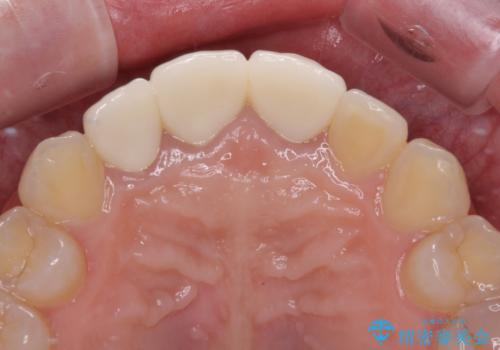

金属を除去したことで、周りと調和した自然な色合いとなり、クラウンの際の位置も歯肉に少し入り込む位置となっているためまるで本物の歯のような仕上がりとなりました。